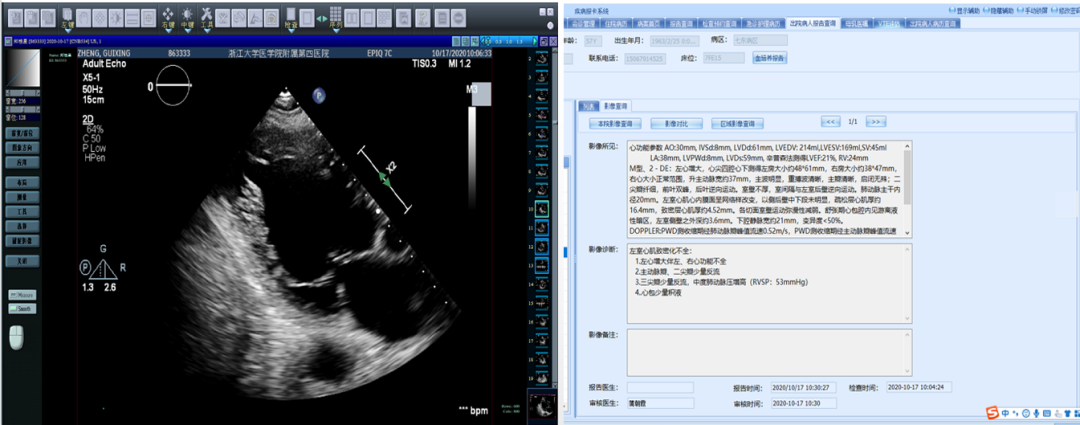

✔ 入院时心脏彩超:LVDd:61 mm;EF:21%。

治疗前后心脏彩超